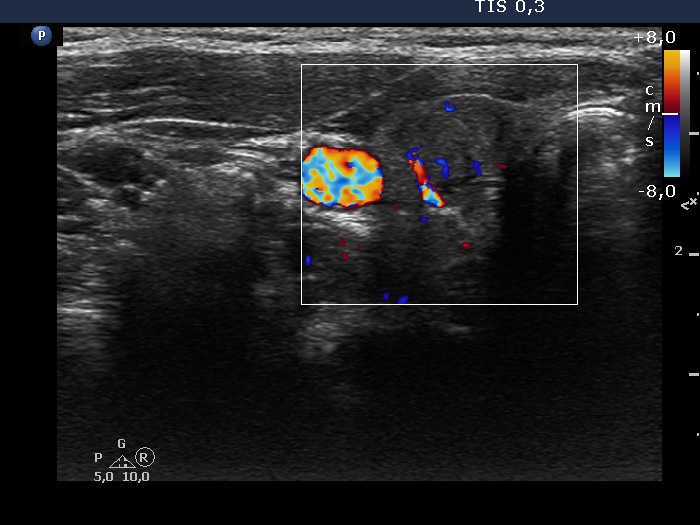

Teamwork - case 894 (ultrasonographic picture 3)

Right lobe, transverse scan, color Doppler mode. The nodule presents signs of intranodular vascularity. There is a large vessel at the edge of the lesion.